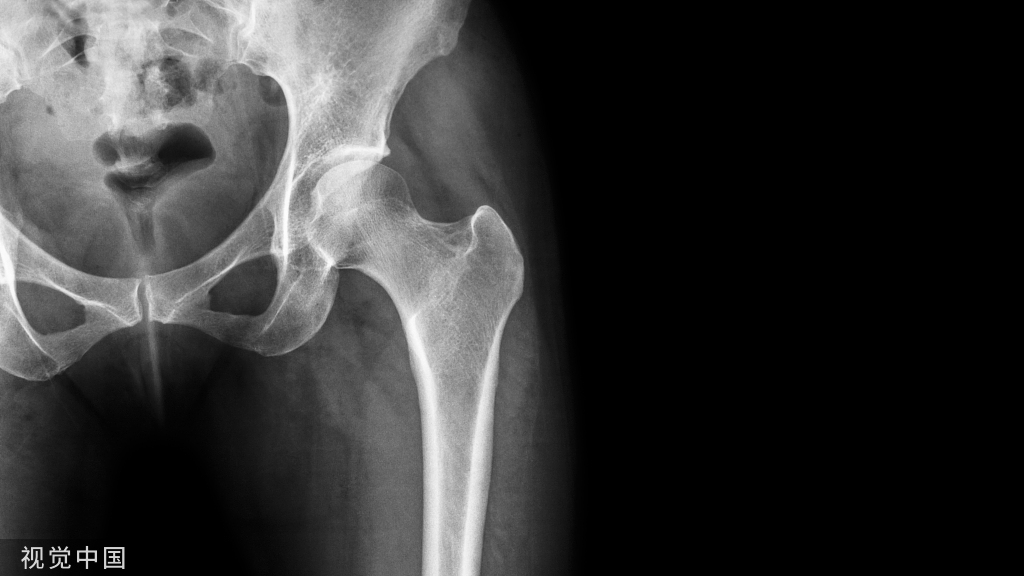

外侧壁骨折时,通常会出现髋内翻

可以在大粗隆处进行勾拉来纠正髋内翻